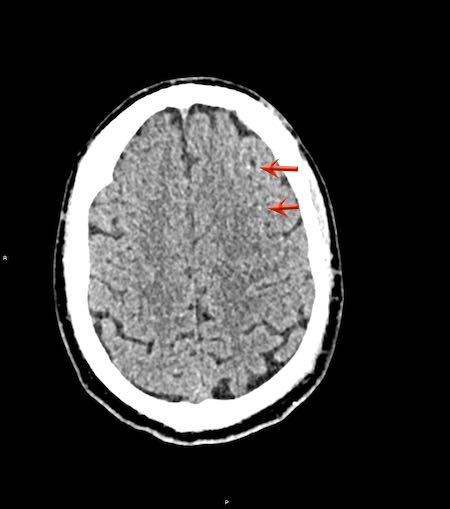

Tụ máu dưới màng cứng đồng tỷ trọng

Khi tụ máu dưới màng cứng tiến triển theo thời gian, tỷ trọng của khối tụ máu sẽ giảm dần và có thể tương đương với tỷ trọng của nhu mô não, khiến việc phát hiện tổn thương trở nên khó khăn.

Đây là trường hợp tụ máu dưới màng cứng đồng tỷ trọng rất khó phát hiện (các mũi tên).

Lưu ý rằng ở mức cắt cao hơn có tụ máu dưới màng cứng hai bên.